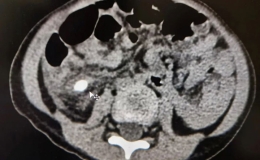

当引流管口“唱反调”——护士巧用造口袋,为患者皮肤筑起“防护堤”